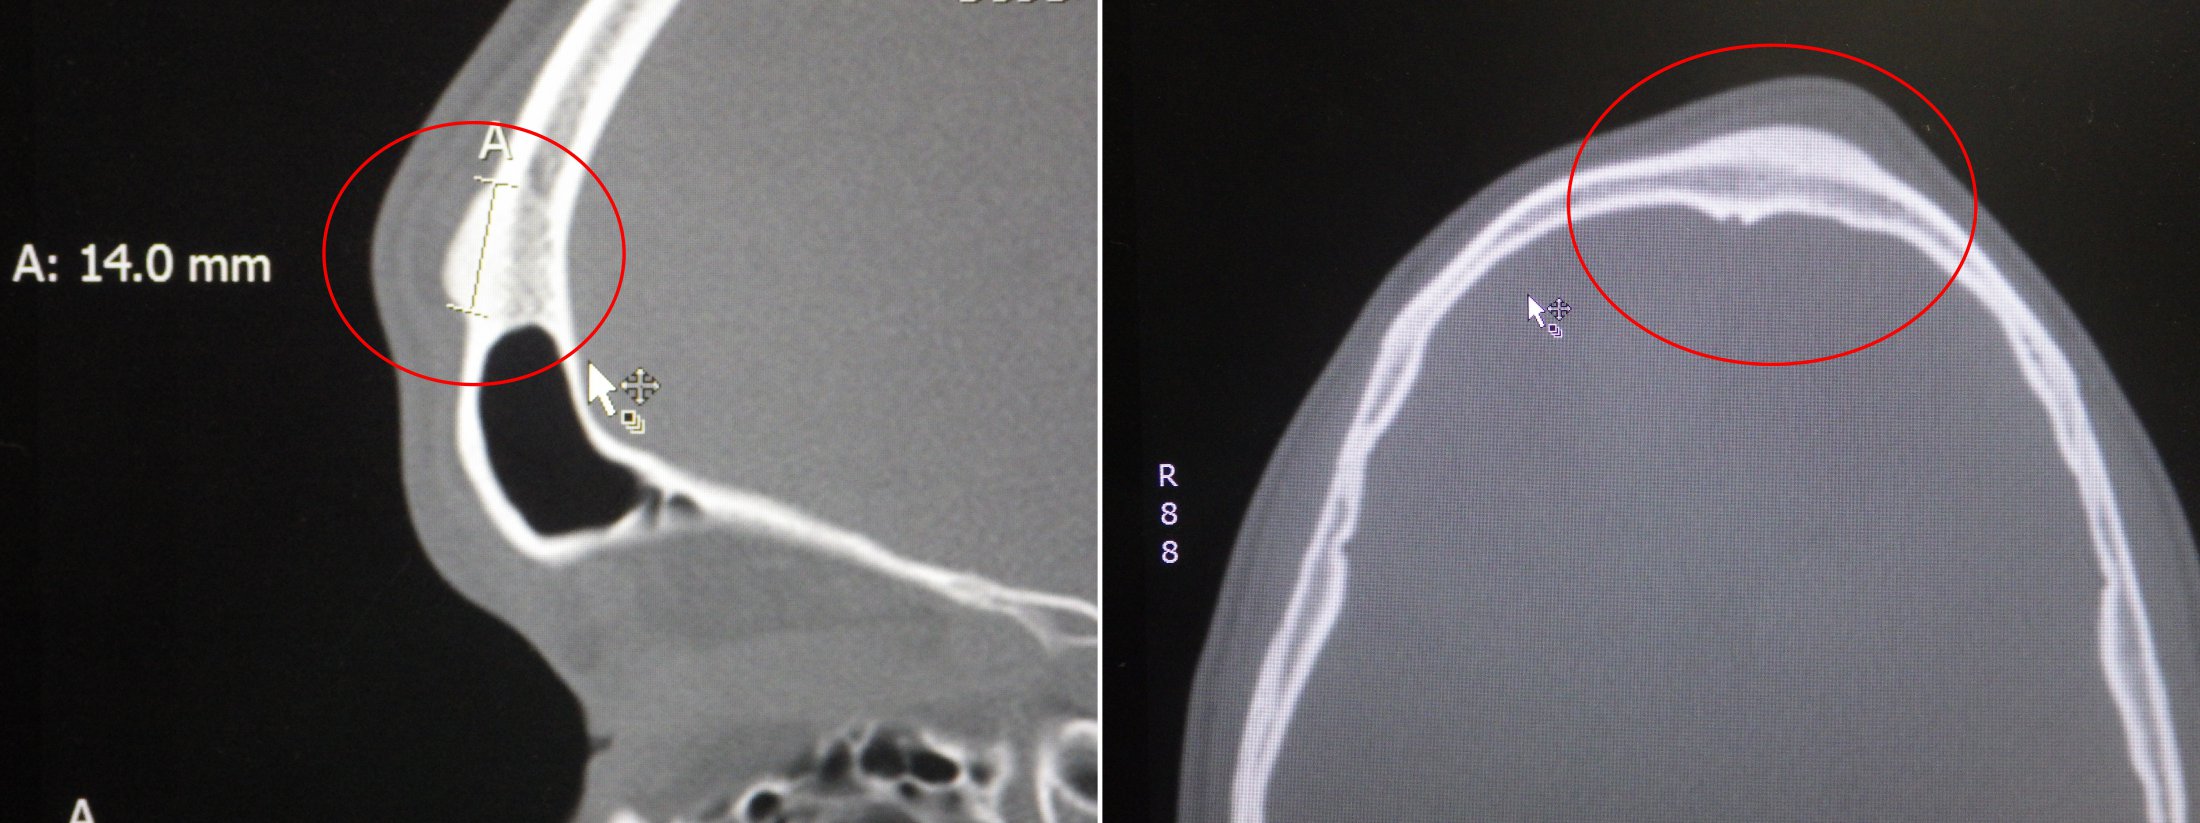

(A) Contrasted computed tomography of the face, showing an osteoma of Should Osteoma Be Removed This uses radio waves to shrink the osteoma tumor. Am i a good candidate for forehead osteoma removal? Osteomas are benign lesions which are generally asymptomatic but for symptomatic lesions,. Fishman commonly removes osteomas in the office. When surgery is required, osteomas can often be removed using minimally invasive endoscopic techniques, passing instruments and scopes through the nostrils without the. Should Osteoma Be Removed.